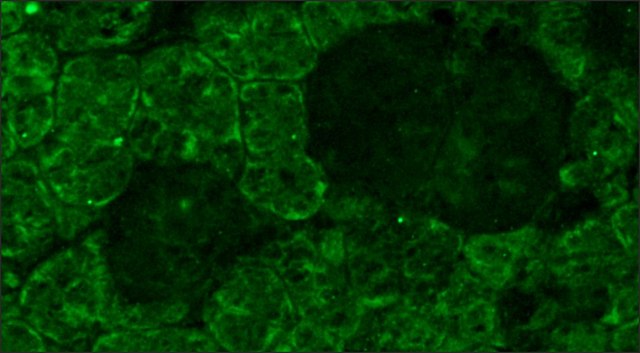

electron microscopy: suitable, immunocytochemistry: suitable using cultured cells, immunohistochemistry (frozen sections): 1:10,000 using frozen sections of rat eye, indirect ELISA: suitable, radioimmunoassay: suitable, western blot: suitable

General description

小鼠单克隆克隆RET-P1抗视蛋白抗体用于标记视蛋白/视紫红质,以通过免疫细胞化学和免疫组织化学(IHC)技术进行检测和定量,例如免疫印迹,培养细胞的免疫细胞化学,免疫组织化学(多聚甲醛/戊二醛固定,多聚甲醛灌注固定,冰冻切片),免疫电子显微镜,ELISA,竞争性ELISA和固相RIA。 它被用作探针,用来确定视蛋白/视紫红质在视紫红质位置、功能特性和控制杆感光细胞分化的分子机制研究中的存在和作用。

小鼠的单克隆抗视蛋白抗体可用于免疫荧光和组织学。